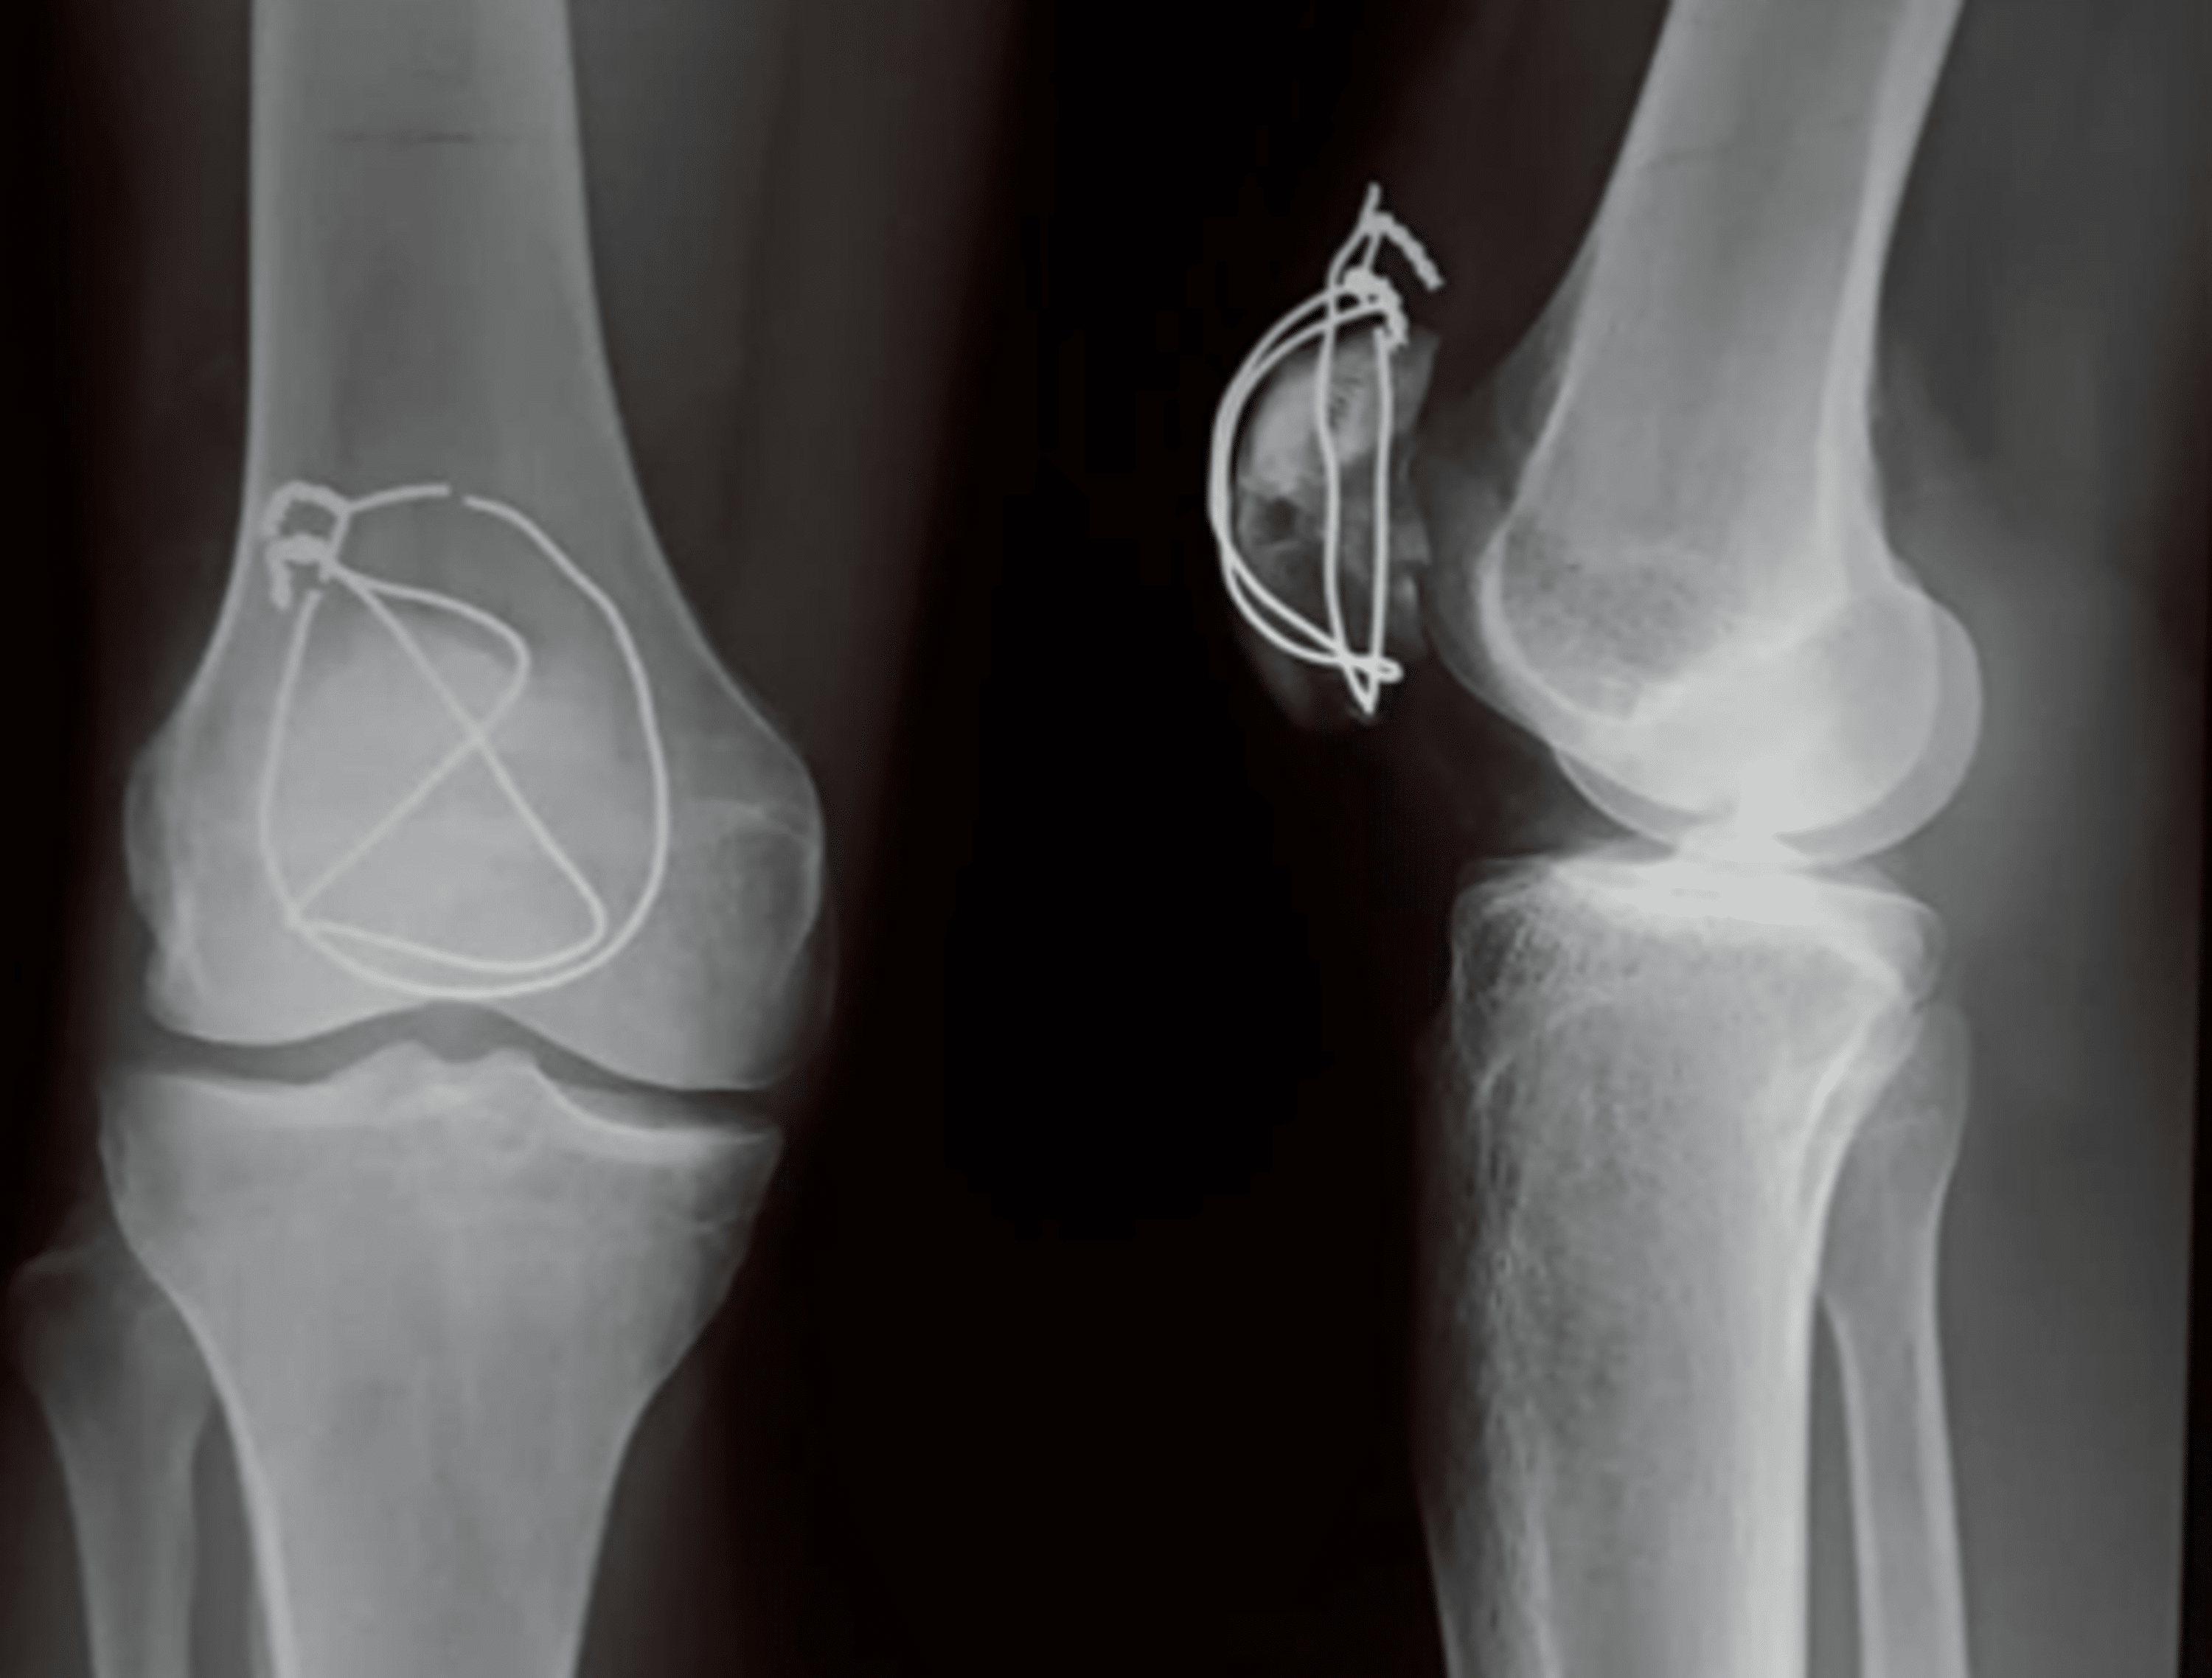

Broken Cerclage Wire . cerclage wiring may be used as a standalone device, or in combination with other fixation systems. cerclage wiring provides additional stability to the reduced fracture through centripetal. Fracture of proximal component of medial wire. Orthopedic wire is used as a supplementation for fracture fixation for. 1 there are various methods for treating a patellar fracture, and the tension band wiring (tbw) technique has been widely used. the following cerclage wiring configurations are described and demonstrated in accompanying videos: principles and clinical application of cerclage wiring. Status post patellar fixation with k and cerclage wires. open reduction and internal fixation (orif) is indicated for fractures with displacements greater than 3 mm, an articular incongruity of 2 mm or more, or a disrupted extensor mechanism.

Preoperative Xrays of a comminuted patella fracture (above). 3 months Broken Cerclage Wire Fracture of proximal component of medial wire. 1 there are various methods for treating a patellar fracture, and the tension band wiring (tbw) technique has been widely used. cerclage wiring provides additional stability to the reduced fracture through centripetal. principles and clinical application of cerclage wiring. Orthopedic wire is used as a supplementation for fracture fixation for. Status. Broken Cerclage Wire.

Broken cerclage wire Image Broken Cerclage Wire principles and clinical application of cerclage wiring. cerclage wiring may be used as a standalone device, or in combination with other fixation systems. Orthopedic wire is used as a supplementation for fracture fixation for. cerclage wiring provides additional stability to the reduced fracture through centripetal. open reduction and internal fixation (orif) is indicated for fractures with. Broken Cerclage Wire.